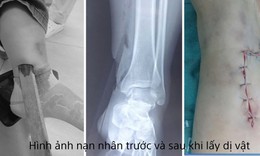

Cứu người bị áp xe ổ bụng hiếm gặp do mắc xương cá

Tin nóng y tế - 09/10/2025 20:05SKĐS - Chiều 9/10, Bệnh viện Lê Văn Việt (TPHCM) cho hay, các bác sĩ khoa Ngoại Tổng hợp vừa phẫu thuật thành công một ca áp xe ổ bụng do dị vật xương cá có thể nguy hiểm đến tính mạng nếu chậm trễ xử trí.